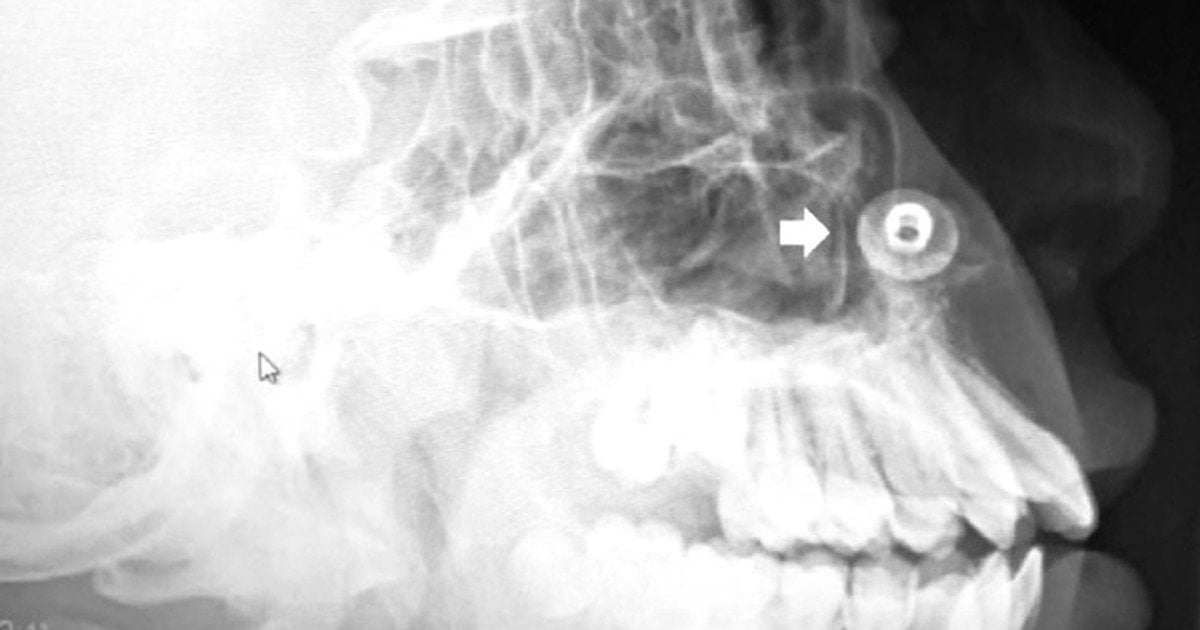

Ринолит это